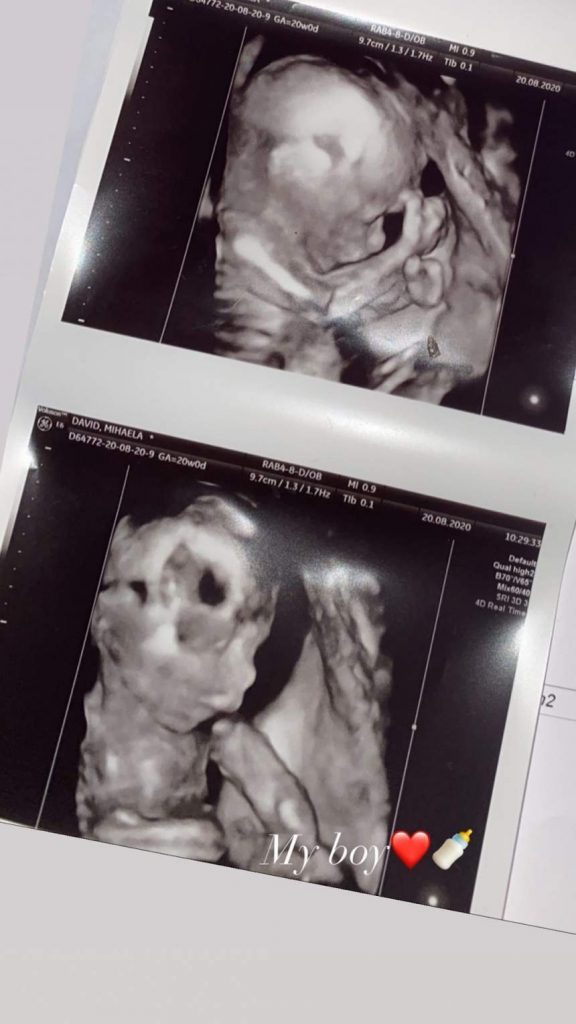

„”My boy”, a scris Dani pe contul de Instagram lângă imaginea pe care au apreciat-o majoritatea dintre fanii săi din mediul online care l-au răsplătit cu inimioare.